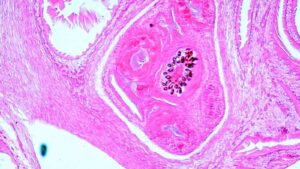

Bildgebende Verfahren (MRT, CT, PET-CT), endoskopischer Ultraschall, Biopsien und Tumormarker gehören zu den am häufigsten genutzten Methoden bei der Diagnose von Bauchspeicheldrüsenkrebs.